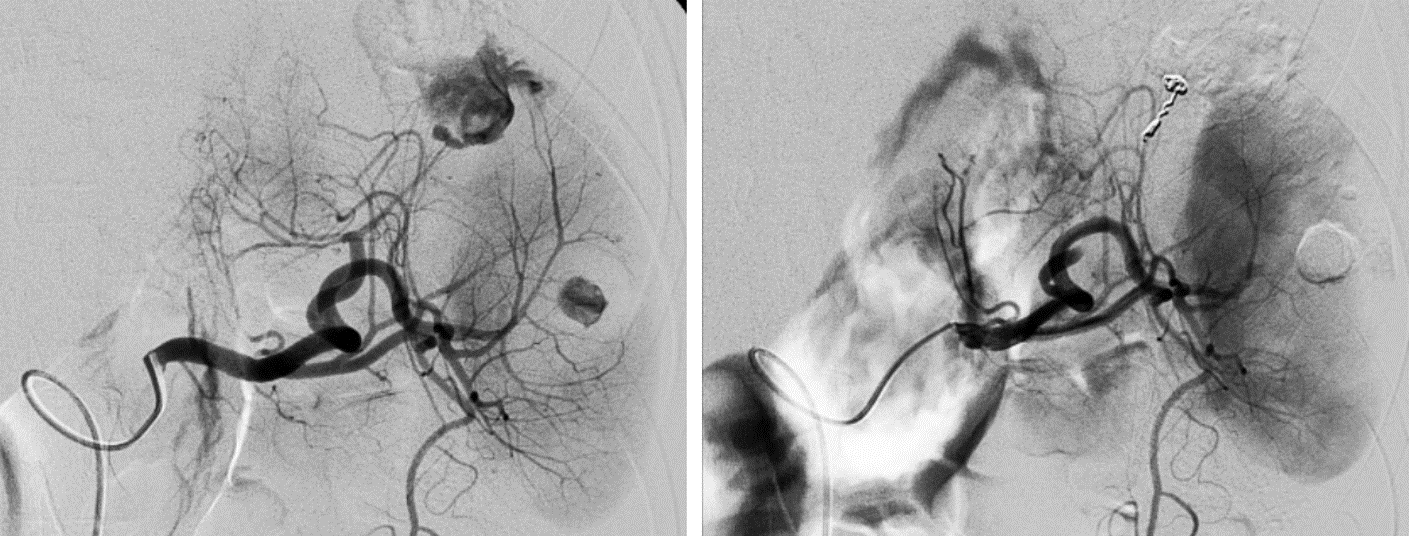

- Artériographie diagnostique : Un cathéter fin est inséré dans l’artère fémorale (ou parfois dans d’autres artères, selon la localisation du saignement) et guidé jusqu’aux vaisseaux responsables du saignement. Cette étape est réalisée avec précision et en temps réel sous contrôle radiologique. Une cartographie artérielle est réalisée afin de bien comprendre l’anatomie vasculaire et de visualiser la zone de saignement. L’objectif est ensuite d’atteindre les artères responsables du saignement avec le matériel adapté.

- Injection de l’agent embolisant : Une fois le cathéter positionné correctement, l’agent embolisant (souvent des microbilles) est injecté prudemment et sous contrôle angiographique permanent dans les vaisseaux sanguins concernés. Cet agent bloque progressivement le flux sanguin vers la zone qui saigne, ce qui permet de stopper les saignements de manière efficace.

- Contrôle post-procédure : Une fois l’embolisation réalisée, une angiographie de contrôle est effectuée pour vérifier que le saignement est bien stoppé et que l’embolisation a été efficace. On vérifie aussi de manière systématique qu’il n’y ait pas d’anastomoses responsable d’une reprise du saignement par des voies détournées. Le patient est ensuite surveillé pendant quelques heures pour détecter d’éventuelles complications.